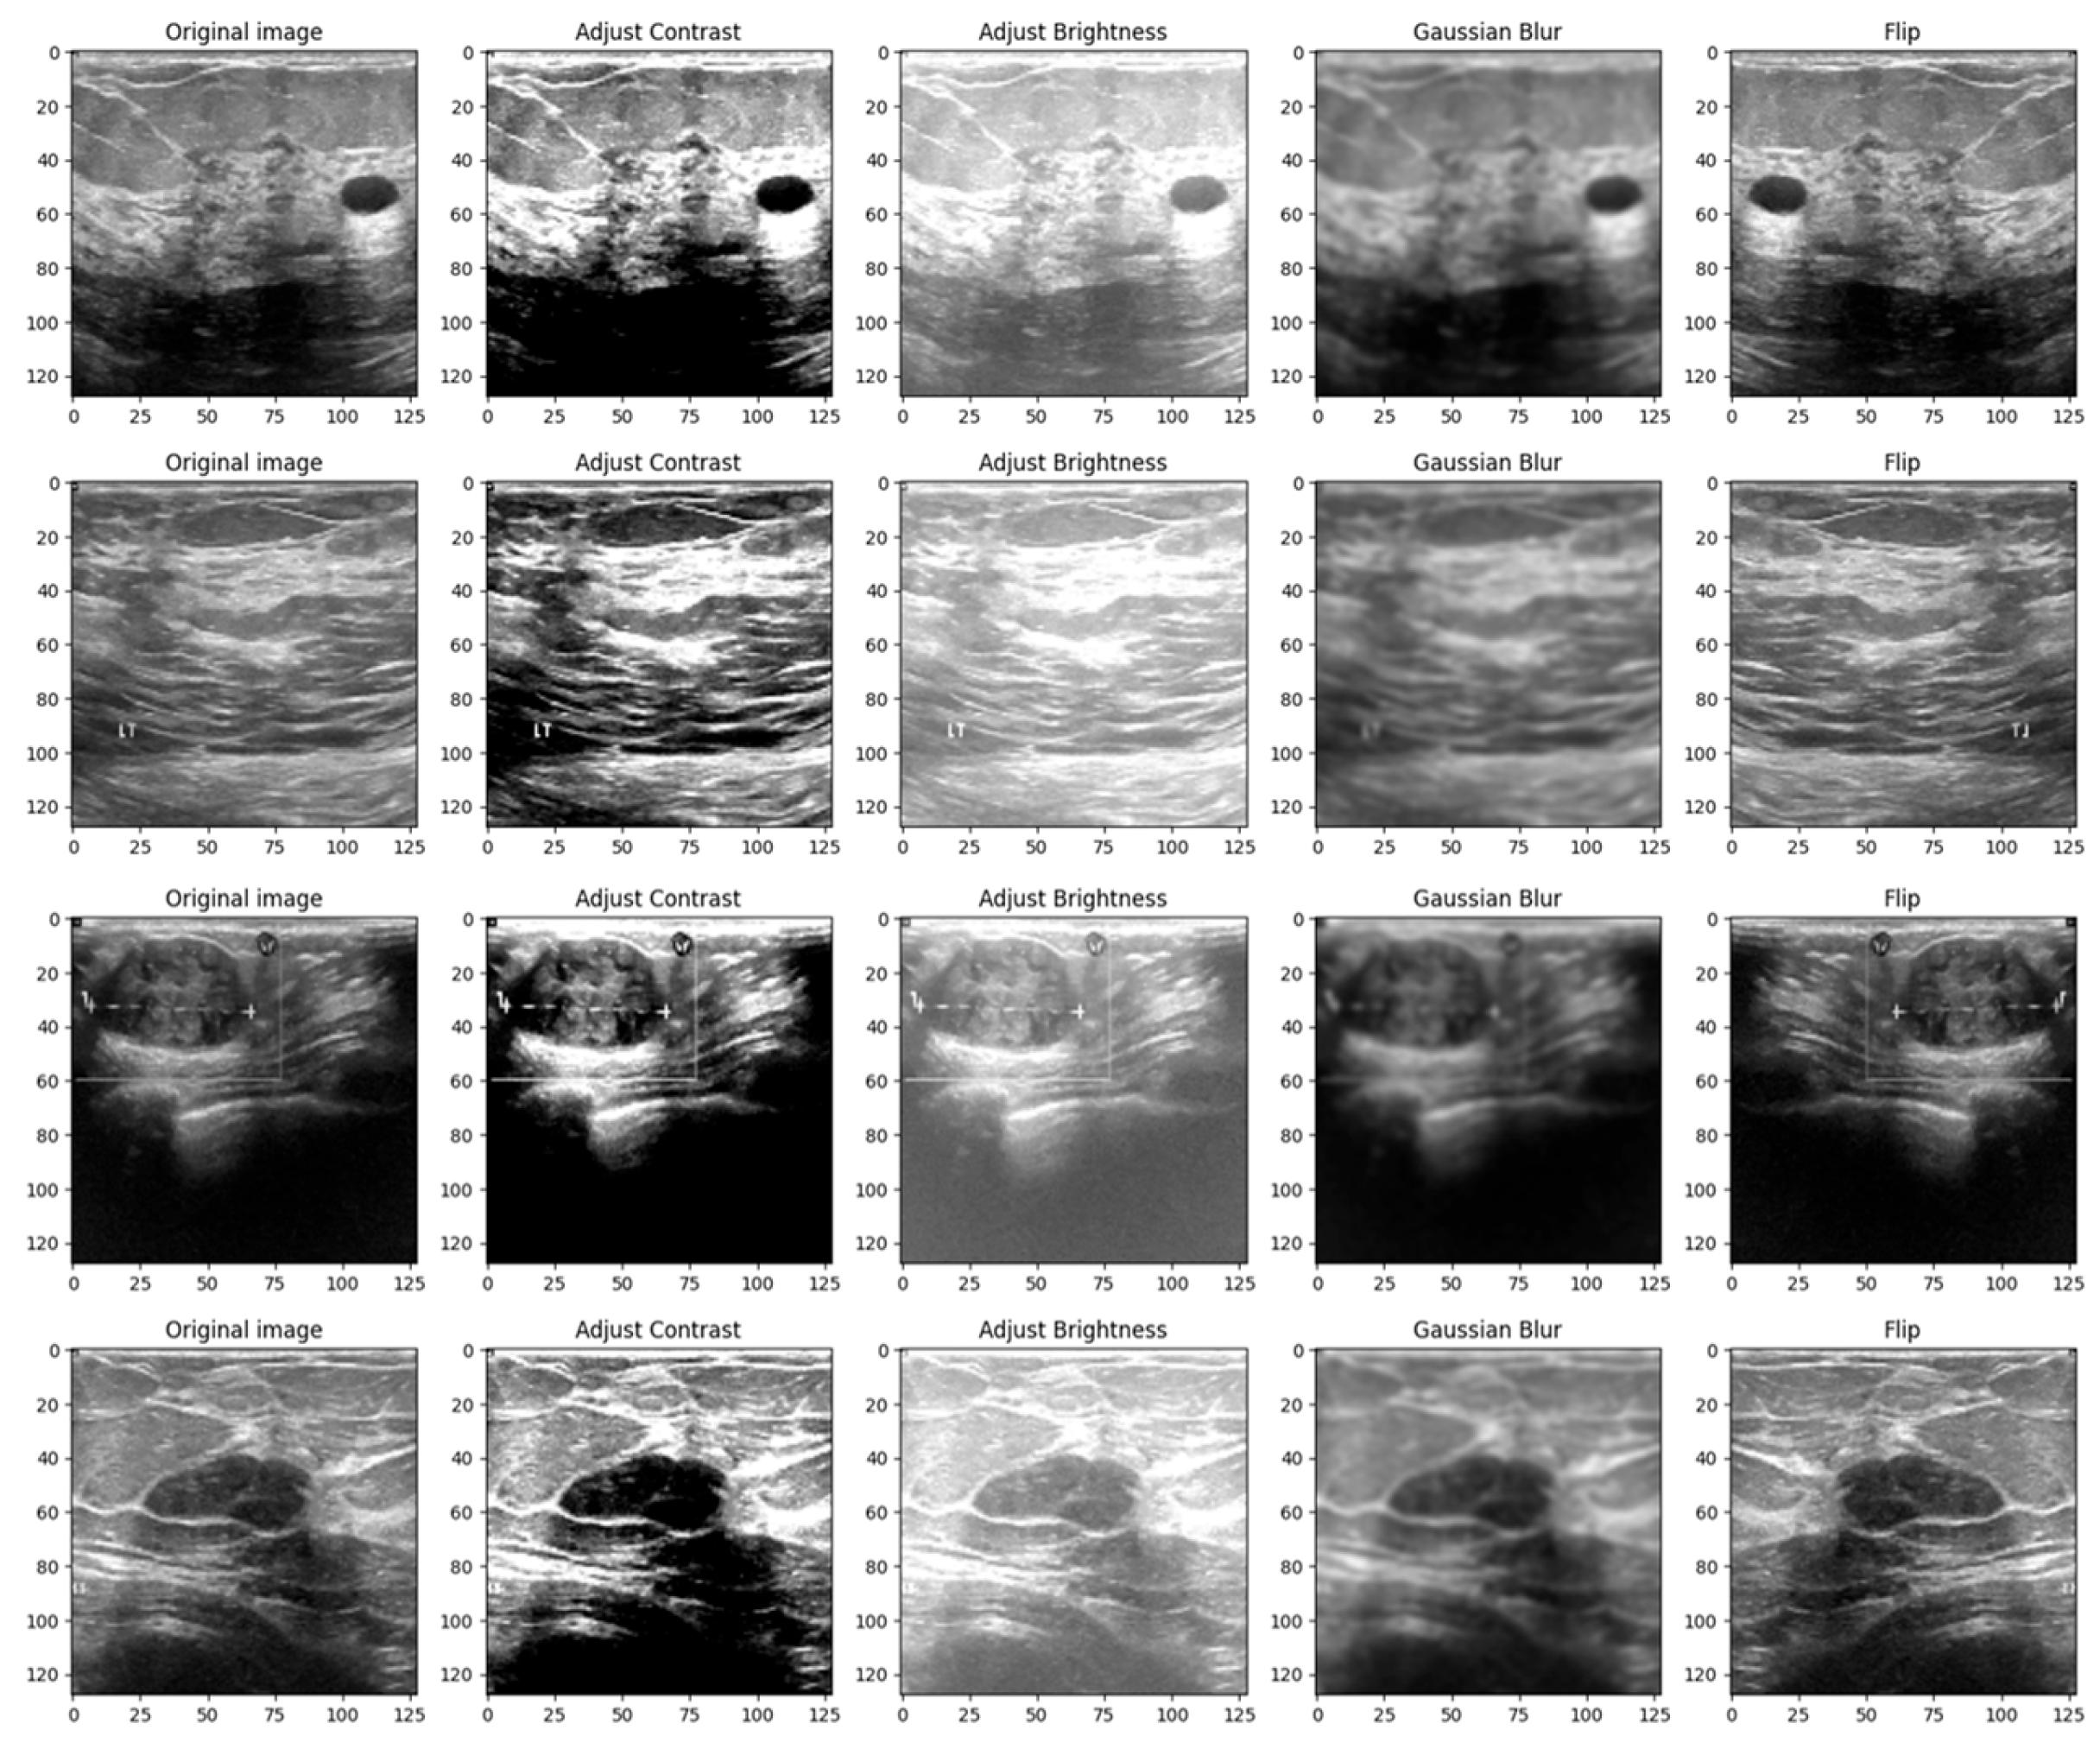

Images, like any other signal, might contain many sorts of noise owing to the source, for instance, the ultrasound camera. Therefore, image smoothing techniques such as Gaussian filters help reduce the noise from images taken in low light, smooth the edges, and help the model to generalize the solution efficiently. The kernel used to apply the filter was chosen to be a 5 × 5 matrix [26]. Figure 4 shows a 4 × 5 grid of random BUS images from the training set, highlighting the augmented samples as well as the original ones.

Figure 4.

Grid of 4 × 5 random showing the effect of data augmentation on the images from the training set.

The reasoning behind the decision to alter the contrast, brightness, Gaussian blur and flip was to adapt the model to scenarios in which the tissue masses are not clear enough or need manual adjustments. Even though most ultrasound machines are preset to specific contrast and brightness values for detecting malignant lesions, sometimes the radiologist might need to make these adjustments manually to make sure that the diagnostic is accurate. Moreover, hypoechoic breast lesions are indicative of potential malignancy. On ultrasound imaging, these lesions typically appear darker than the surrounding isoechoic fat [27]. Therefore, in order to train a robust model, contrast and brightness variations should be included. Gaussian Blur was introduced to adapt the model to certain perturbations during screening, such as patient movement. Finally, flip was introduced in order to vary the location of the malignant/benign tissue masses.